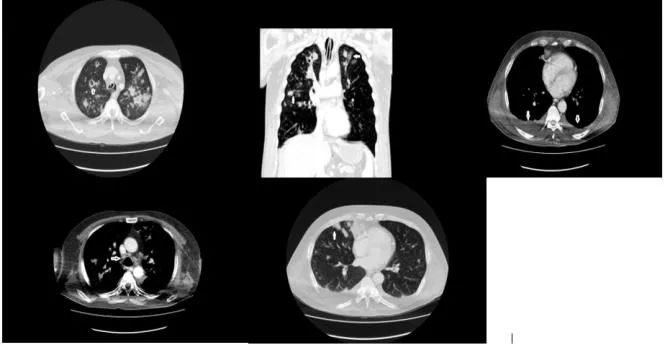

ICU内检查发现:CRP:137mg/dL,白细胞33400/mm²,中性粒细胞32% 。因此由头孢曲松转为使用美罗培南联合利奈唑胺进行治疗,次日行胸部CT检查可见周围及部分空洞结节、浸润、纵隔淋巴结肿大(最大直径1 cm)、双侧胸腔积液及供血血管征(图3)。由于胸腔积液很少,所以没有进行胸腔穿刺术。

图3 CT检查发现空洞结节、浸润、供血血管征、双侧胸腔积液、纵膈淋巴结肿大。

在胸片中,可能不会发现明显的异常,更建议使用CT进行检查。常见胸部CT表现为周围结节、空洞和供血血管征,严重时可出现肺门或纵隔淋巴结肿大。本例胸部CT表现为部分空洞性结节、纵隔淋巴结肿大(最大直径1 cm)、浸润和双侧胸腔积液。